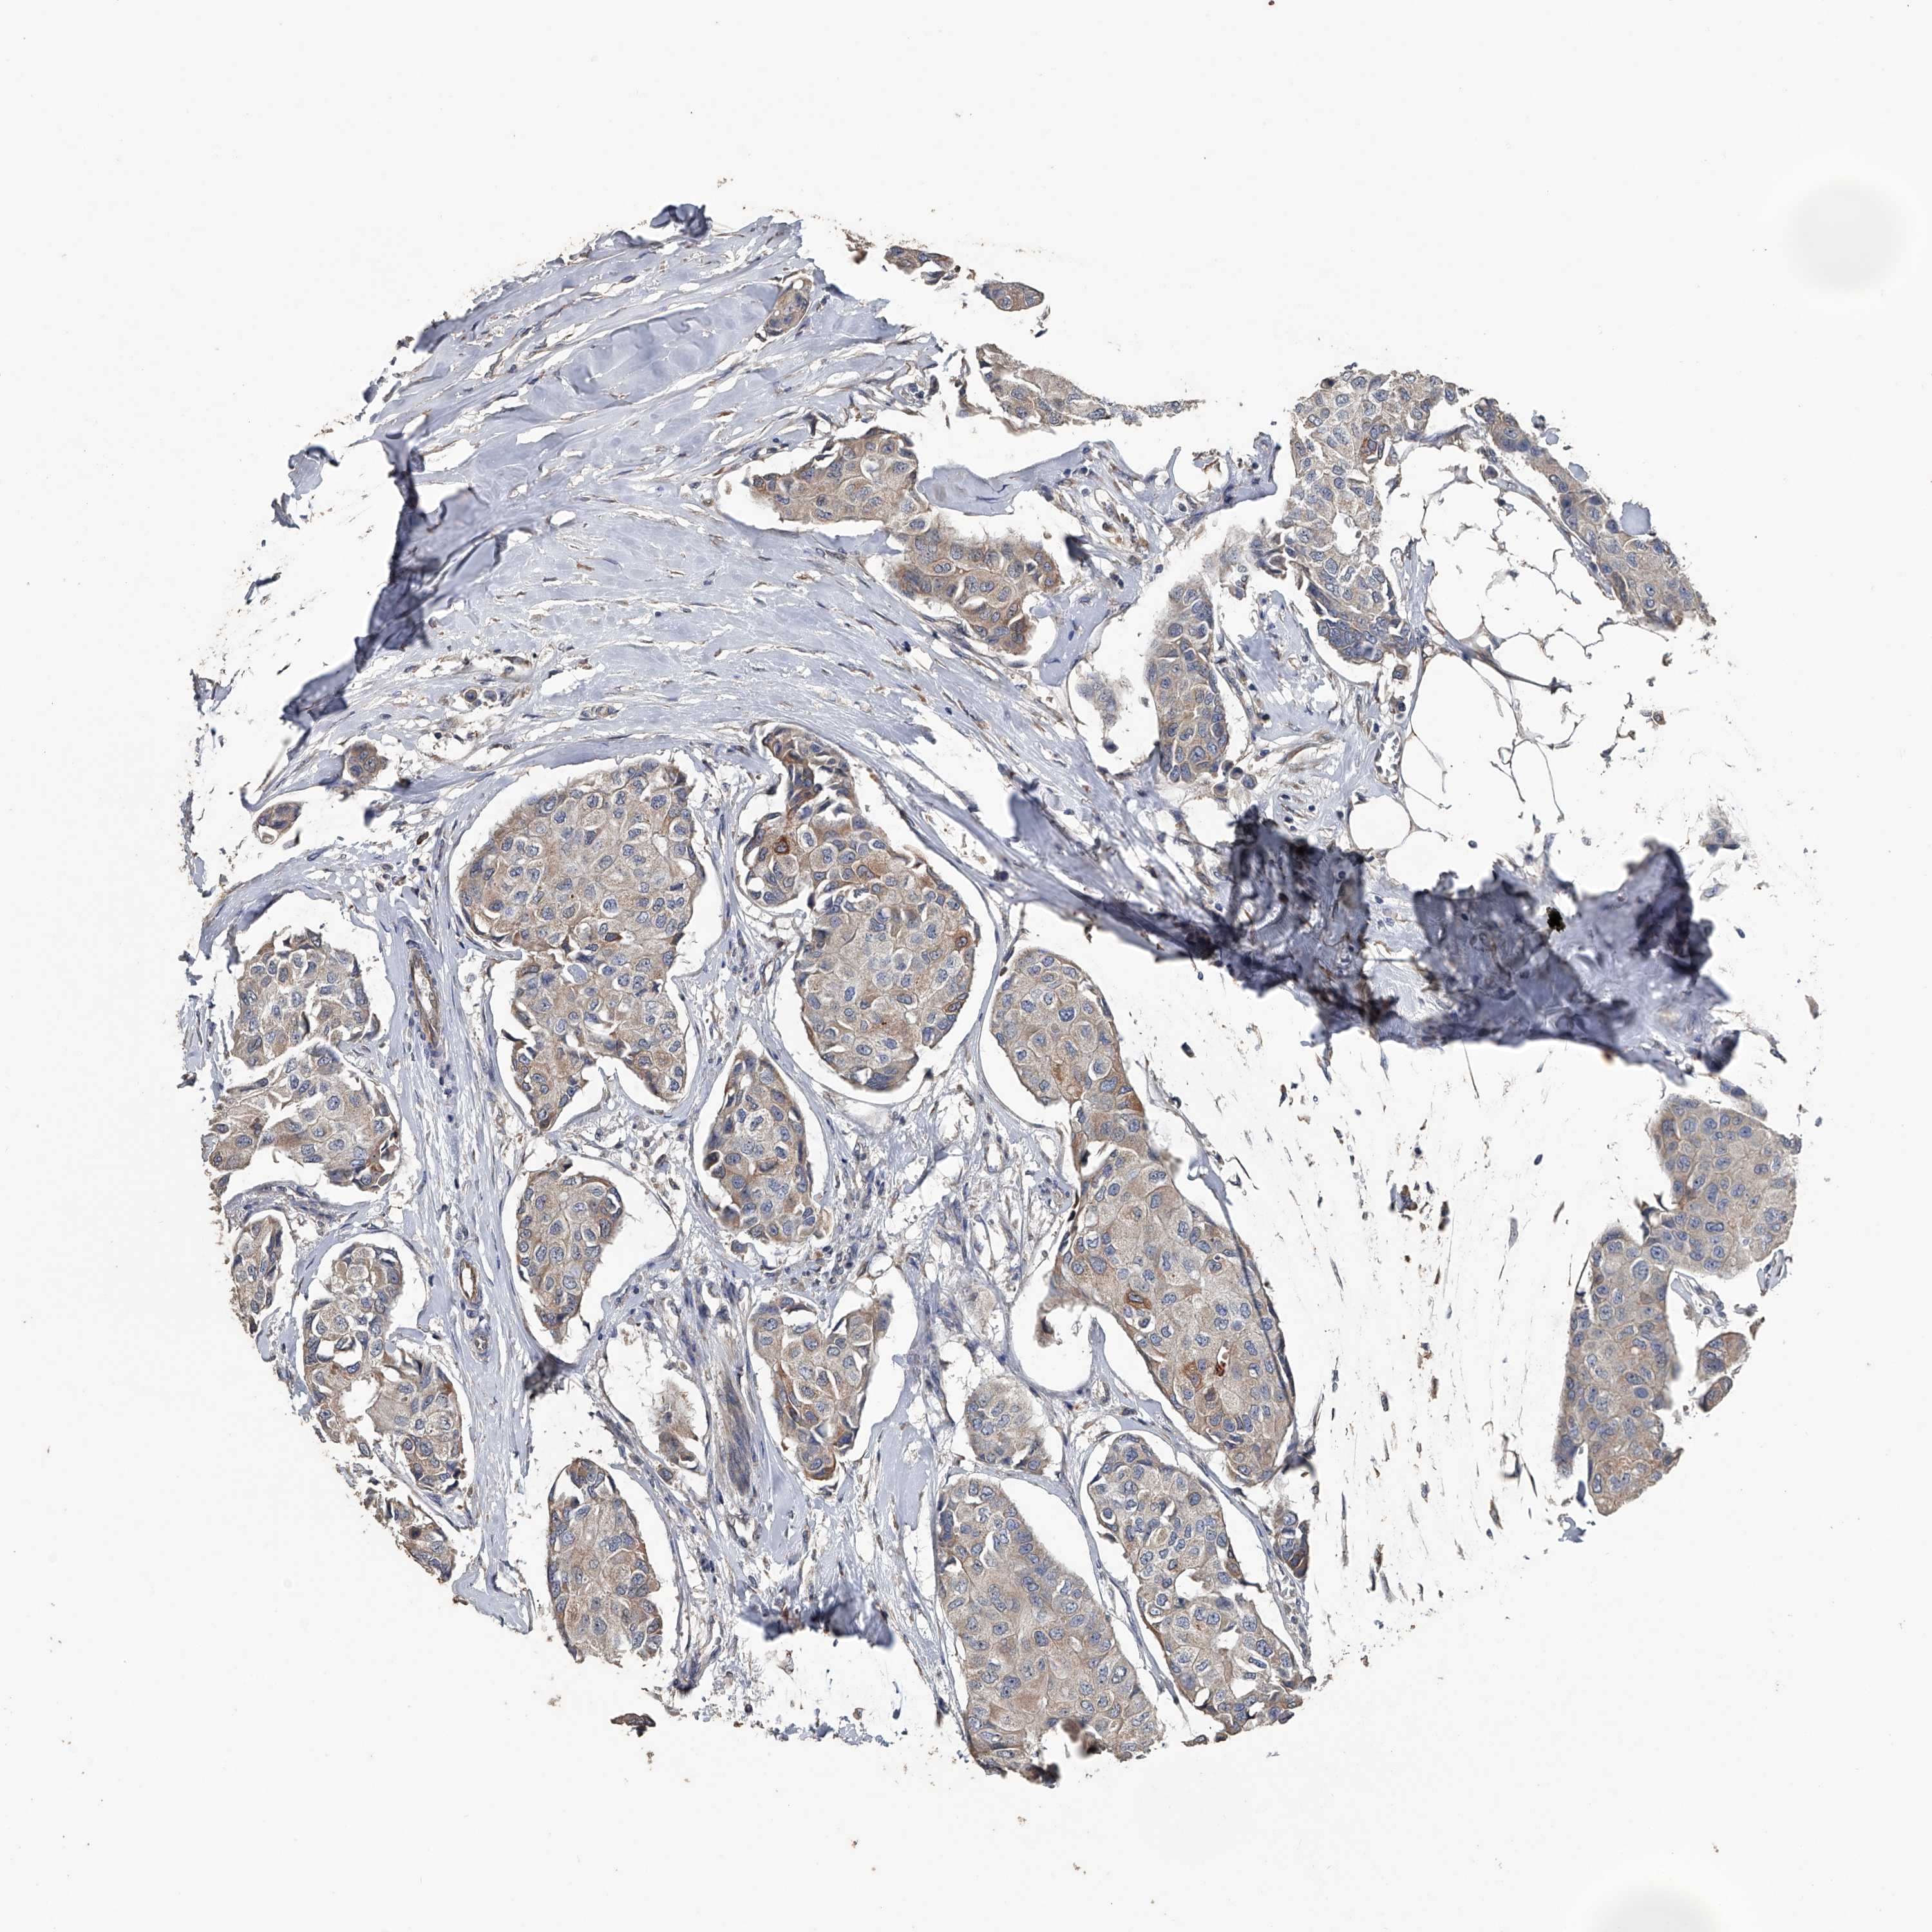

CANCER BREAST CANCER Show tissue menu

Breast cancer

Human cancer